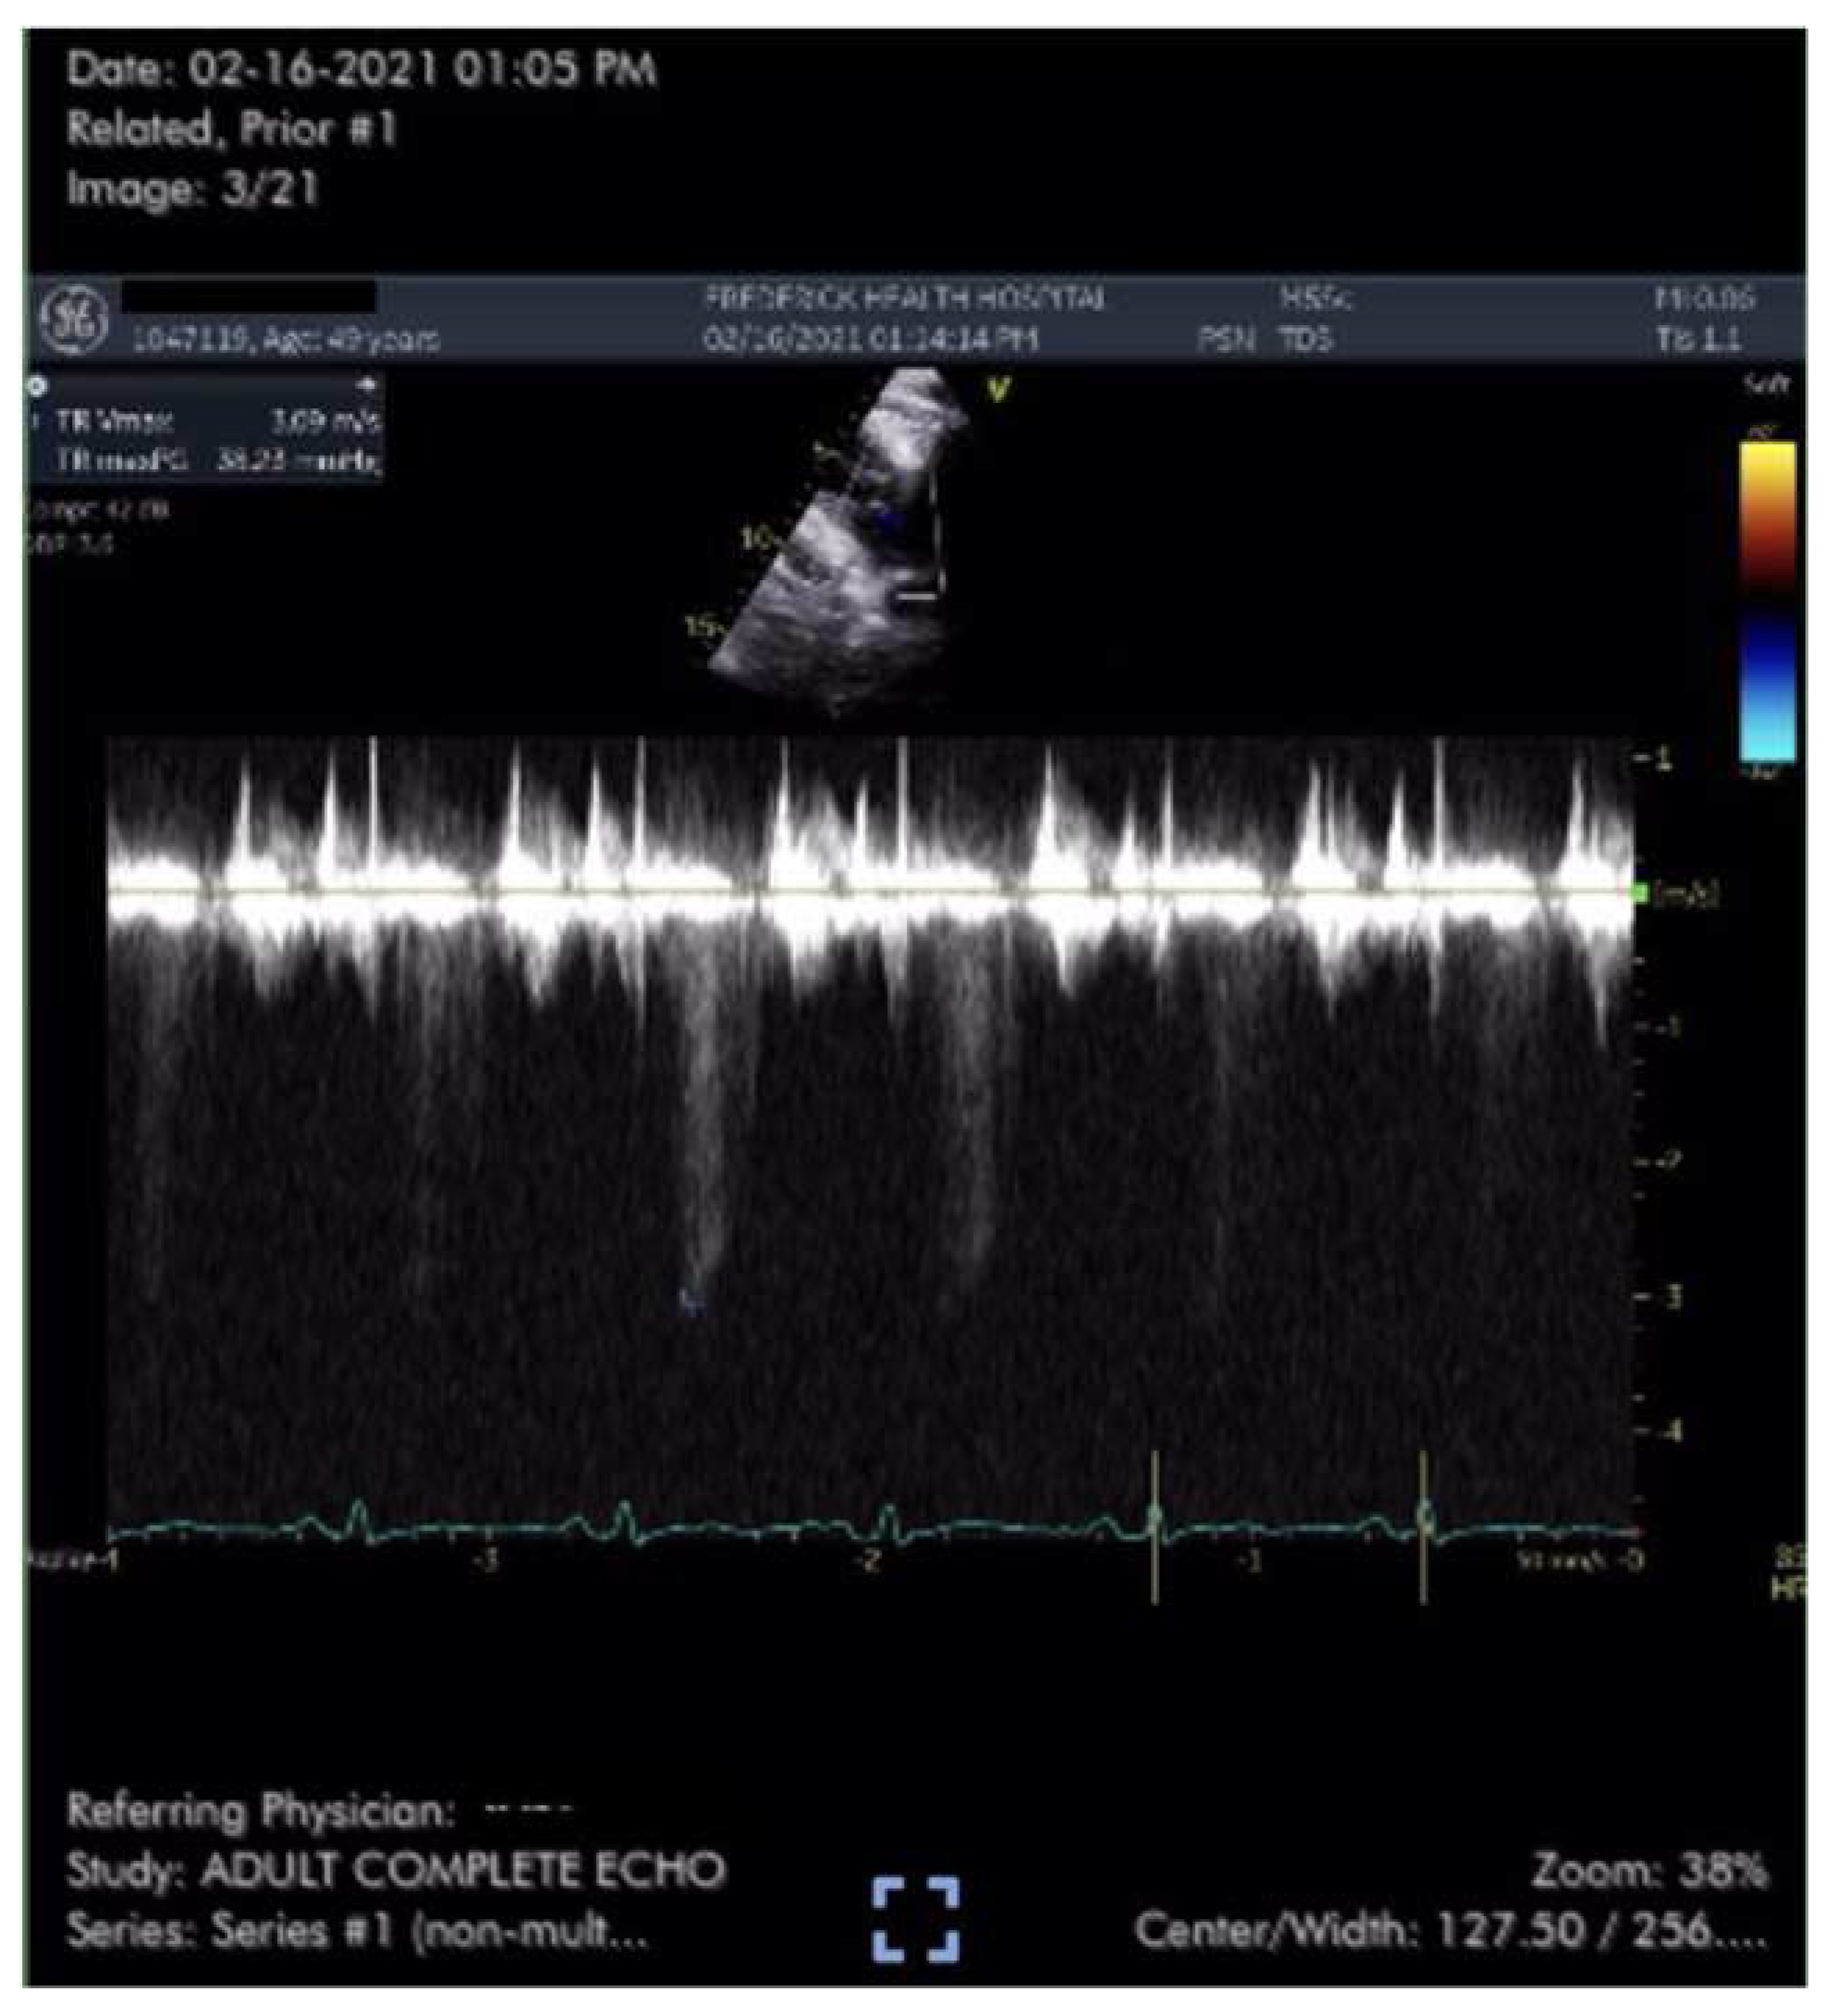

Case #1 is a previously healthy 49-year-old male physician athlete, body mass index (BMI) 23, non-smoker with a history of mild exercise-induced asthma treated with albuterol. Patient completed the primary series of Pfizer mRNA COVID-19 vaccine (BNT162b2) in January 2021. Approximately three weeks after the second dose patient suddenly developed severe fatigue, flu-like symptoms, tachycardia, palpitations, orthostasis, right-sided chest pressure and dyspnea on exertion. COVID PCR testing was negative. Transthoracic echocardiogram revealed normal left ventricular function with an ejection fraction (EF) of 65%, normal right ventricular size and function and a tricuspid regurgitation (TR) jet of 3.09 m/s (Figure 1). Estimated right ventricular systolic pressure (RVSP) of 42 mmHg was interpreted as mild/moderate pulmonary hypertension (Table 1). Laboratory studies including brain natriuretic peptide (BNP) 22 pg/ml (reference range <900 pg/ml) were unremarkable except for elevated low-density lipoprotein (LDL) cholesterol and hematocrit of 50%. Pulmonary computer tomography (CT) angiogram with 3D reconstruction of the PA tree was normal without evidence of pulmonary clots (Figure 2 and Figure 3). Patient subsequently developed 15 lbs of fluid gain and generalized swelling, neck pressure, headaches and a feeling of “being hung upside down” consistent with jugular vein distention (JVD) and cerebral venous congestion. The resting oxygen saturation (SpO2) was 92% and there was new onset systolic and diastolic arterial hypertension. Symptoms and chest pressure occurred at rest and were exacerbated by exertion. Exercise and functional limitations were consistent with New York Heart Association (NYHA) Class 3-4. Serial echocardiograms showed no worsening of RVSP and continued normal RV function (Table 1). Symptoms and exercise tolerance improved to NYHA class 1-2 over one year. Fluid weight gain, swelling, tachycardia and arterial hypertension resolved and the resting SpO2 increased to 98-100%. Flu-like symptoms and fatigue diminished but did not disappear. RVSP remained elevated and essentially unchanged by follow up echocardiography (Table 1).

Figure 2. Coronal CT image from 3-D PA reconstruction revealing normal cardiac and PA anatomy without perfusion defects.